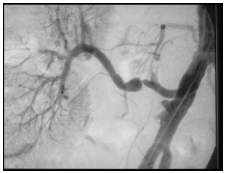

Paciente transplantado renal em 2006, a partir de um doador cadáver, com tempo de isquemia fria de 34 horas, leva quase 2 semanas para reestabelecer a função renal. Evoluindo bem a partir de então, até apresentar há 4 meses um episódio de rejeição revertido com altas doses de corticoide. Em seguida, o mesmo começa a ter importantes picos hipertensivos de controle difícil com tratamento medicamentoso e queda da função renal. Nefrologista que acompanha o paciente solicita ultrassom do rim transplantado que está normal. É então feito arteriografia renal, conforme ilustração abaixo, e uma biópsia do rim transplantado. Marque a alternativa INCORRETA.

Enunciado 1555123-1